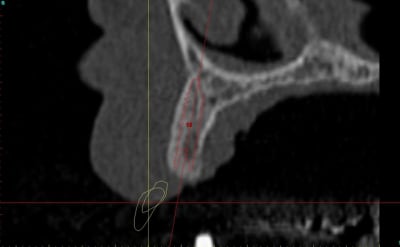

dentiste57 écrivait:

--------------------

> et là ?

> greffe selon ta méthode ?

Cross section dhvkc8 - Eugenol

3d dt3qom - Eugenol

Overview uqcp6u - Eugenol

> dentiste57 écrivait:

> --------------------

> > et là ?

> > greffe selon ta méthode ?

expansion, c'est plus cool!